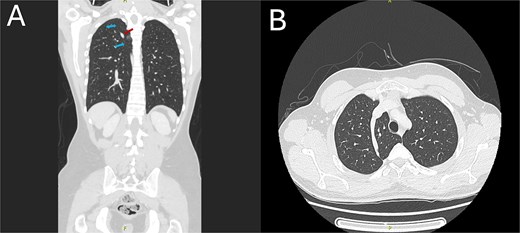

The CT scan revealed an azygos lobe in the right upper lung, definitively ruling out pneumothorax. The azygos vein was situated at the inferior edge of the curvilinear azygos fissure, which extended toward the right tracheobronchial angle (Fig. 2). With preserved lung markings within the lobe, ruling out pneumothorax, a retrospective study of the CXR verified that the lucency matched the azygos fissure.

CT chest demonstrating the azygos lobe. (A) Coronal view with blue arrows indicating the azygos fissure and the red arrow pointing to the azygos vein. (B) Axial view shows the azygos fissure is seen as a curved, sharply marginated line in the right upper lobe, typically situated anteromedially.